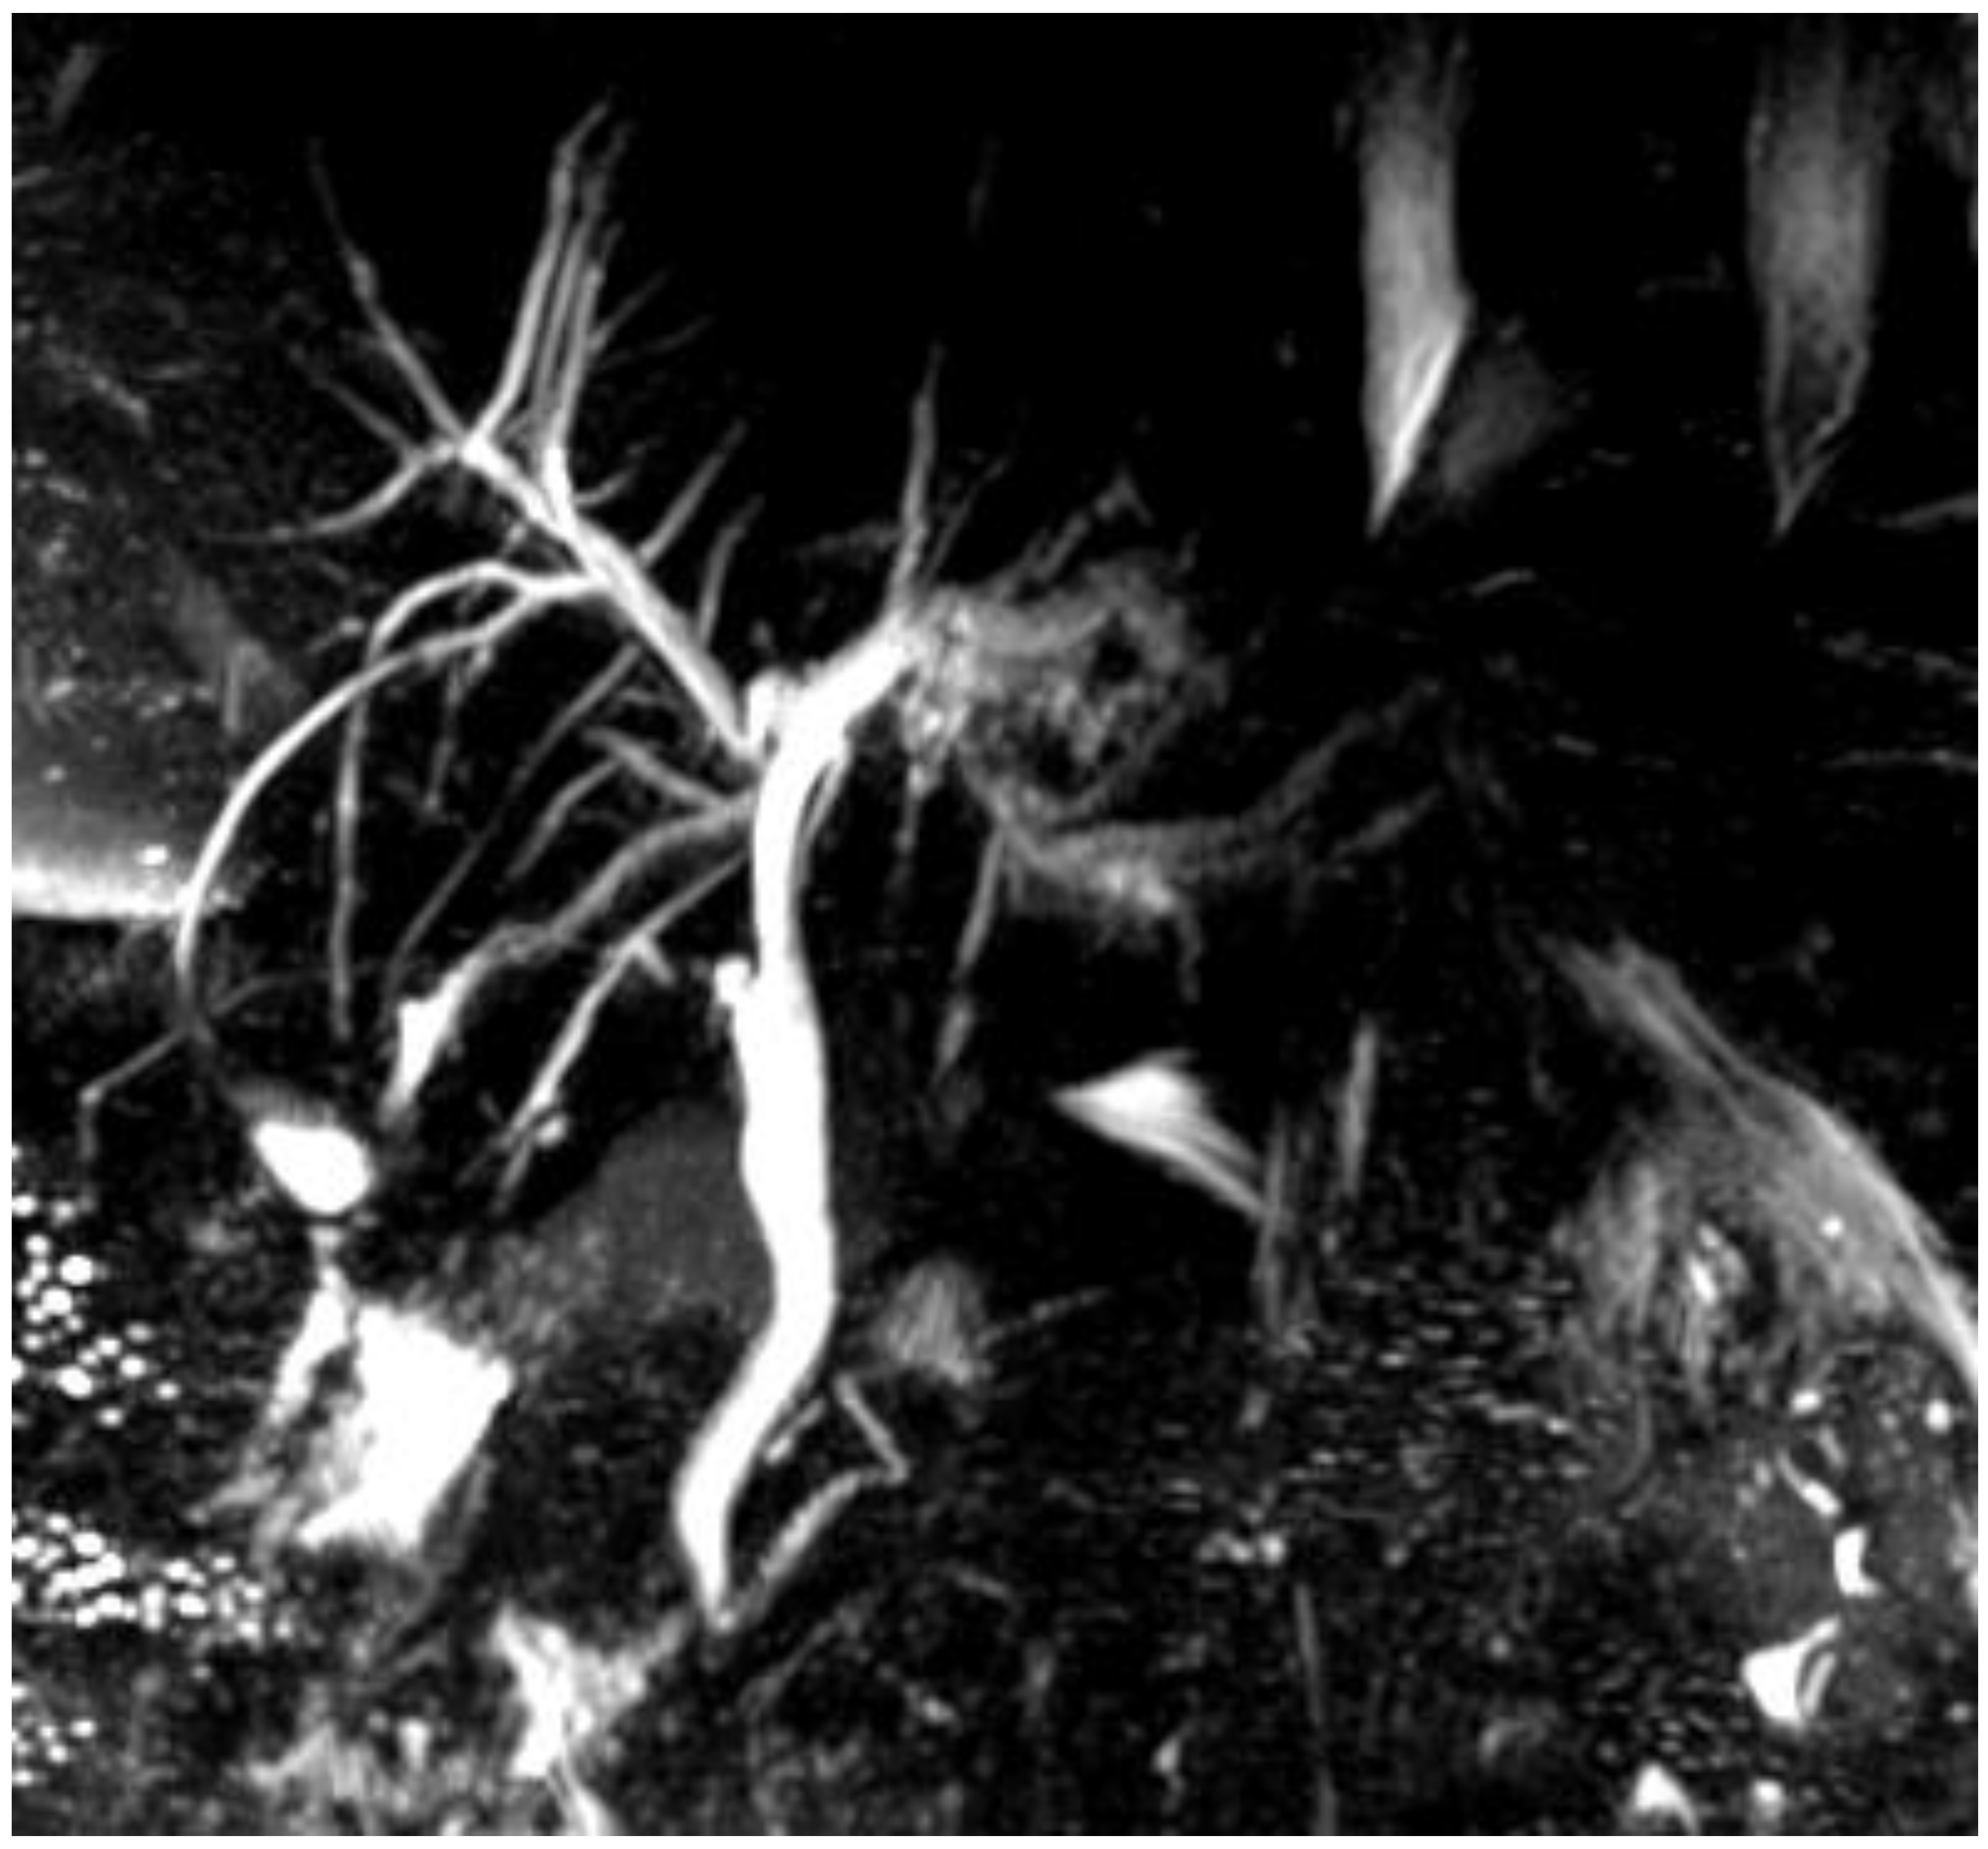

| Imaging performed | Abdominal MRI + MRCP | Abdominal CT | Abdominal CT | Abdominal MRI + MRCP | |||

| Appropriate imaging modality and features | MRCP, ERC. Beaded appearance, pruned tree appearance, and band-like stricture. | MRCP. Diffuse or segmental narrowing of the intrahepatic and/or extrahepatic bile duct, associated with the thickening of the bile duct wall. | MRCP. Intraductal calculi and bile duct strictures. | CT-scan, MRI. The CT-scan: lesions with variable c.e., may present as hypovascular with delayed enhancement because of fibrosis. The MRI may produce hypointense on T1 sequences with moderate-to-high hyperintense on T2 sequences. | CT scan (scarce sensitivity for non-calcific stones) and MRCP. | CT scan, MRCP. MRCP most accurate, shows an extrinsic narrowing of the common hepatic duct, a gallstone in the cystic duct, dilation of the intrahepatic and common hepatic ducts, with a normal common bile duct. | CT scan and portal MR and MRCP. Show portal cavernoma, paracholedochal and/or epicholedochal dilations, portosystemic shunts and abnormal morphology of the bile duct. |